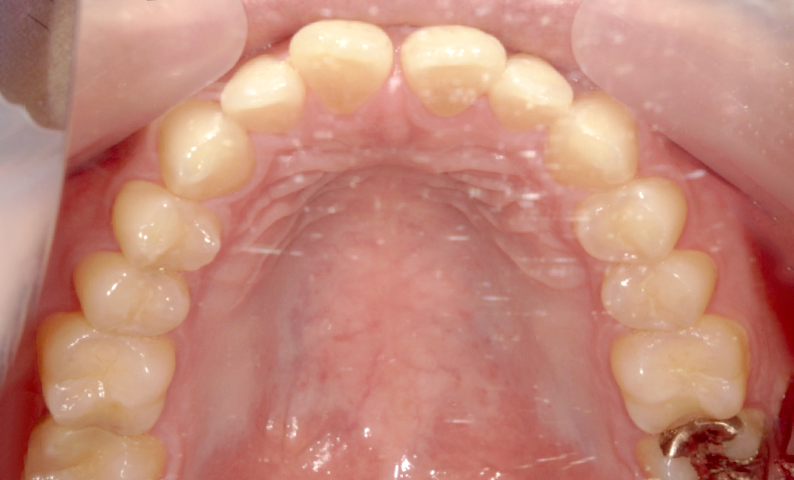

| 治療前 | 治療後 |

|---|---|

|